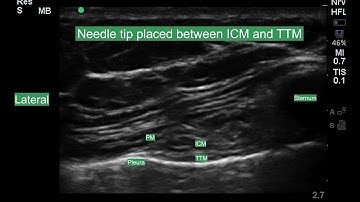

Transverse In-Plane Approach to Thoracic Paravertebral Block